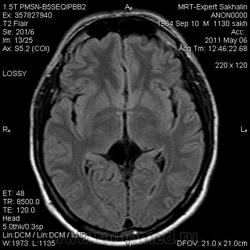

Киста промежуточного паруса?

Мужчина.В анамнезе лет 5 назад травма.Со слов тогда же на МРТ диагностировали кисту промежуточного паруса.А не может ли это быть посттравматическими изменениями?

Киста промежуточного паруса, с внутренними перегородками и минимальной компрессией передних бугорков четверохолмия и шишковидной железы.

Посттравматические изменения данной области ? Врядли... Локализация не характерная, если только имело место диффузно-аксональное повреждение, но периферийного глиоза нет....

Да, есть участки повышенного сигнала на FLAIR есть. Но это скорее всего разрастание нейроглии в ответ на компремирующее воздействие кисты. Посттравматический глиоз, тем более если такая обширная киста, был бы куда больше.

Здесь меня смущают 2 вещи. Во-первых, глиозные изменения правой половины валика мозолистого тела, во-вторых - неправильная форма кисты. Она не симметричная, и стенки ее неровные.

Я думаю, что здесь не киста паруса, а арахноидальная киста, либо эпидермоид. Для исключения эпидермоида можно сделать DWI, и тогда мы увидим повышенный уровень сигнала от кисты.

И еще. В нашем случае валик мозолистого тела явно поддавлен и расположен спереди от кисты, тогда как в случае кисты промежуточного паруса он всегда расположен сзади и сверху от нее.

В принципе, киста промежуточного паруса не должна рости, а арахноидальная и эпидермоидная, если растут, то очень медленно. В нашем случае главной задачей является именно установления наличия или отсутствия роста. Дифференциация вида кисты имеет более-менее схоластическое значение;)

Кисты эпифиза обычно гораздо меньших размеров, и распространяться они должны, по идее, во все стороны от него. Здесь же эпифиз явно поддавлен книзу.

Возможно это кистозное образование пинеальной области с незначительным перифокальным глиозом и единичными перегородками. Хотелось бы посмотреть на контрастное усиление. Часто ли встречаются арахноидальные кисты с глиозными изменениями по периферии?